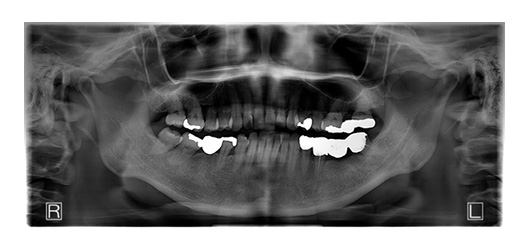

70代男性(インプラント)

- 患者さん情報(年齢・性別)

- 70代 男性

- 主訴

- 歯を失ってしまったところにインプラントに入れたい

- 治療箇所

- 7箇所

- 治療方法

- インプラント

- 費用

- 約320万円

- 治療期間

- 約1年

- その治療によるリスク・副作用

-

- 治療期間がながい、外科的治療が必要